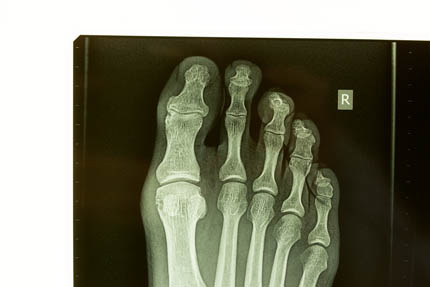

irrefutable evidence June 13, 2014injuryfucked, x-raystriker Almost a year later the foot is still sore, X-rays show “…early osteoarthritis involving the distal interphalangeal joint of the big toe and a fracture near the head of the proximal phalanx…”. Awesome.